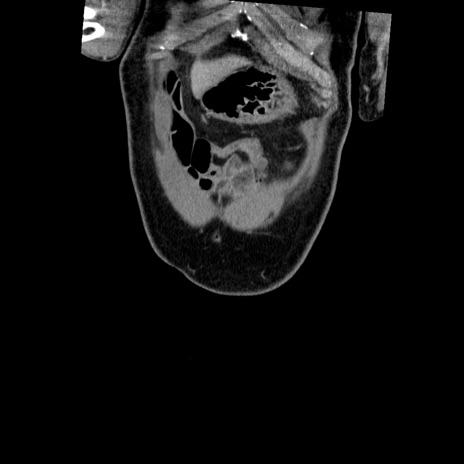

症例22(冠状断像)

【症例】50歳代男性

【主訴】腹痛

【現病歴】AVMからの被殻出血のため回復期リハ病棟入院中。 本日午後3時頃急に下腹部痛が出現した。

【既往歴】AVM、被殻出血、虫垂炎、高血圧

【身体所見】意識晴明、左半身不全麻痺、会話の理解は良好、36.5°C、腹部:膨隆、全体に板状硬、下腹部正中に圧痛点あり、反跳痛-、筋性防御不明、右下腹部にope scar

【データ】WBC 9400、CRP 0.06

横断像